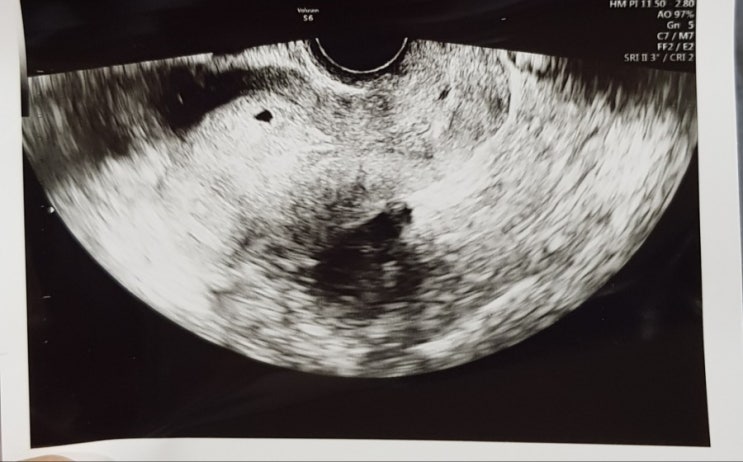

배란19일째 아기집보다!♡

안녕하세요 어제가 저는 배란19 일째였어요 다들 병원 늦게가라고 하시던데 저는 왼쪽배가 콕콕아파서 혹시...